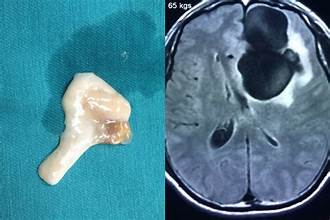

Hình ảnh: Sán dây lợn được phẫu thuật lấy ra từ não một người đàn ông hay ăn tiết canh (chụp cắt ngang hộp sọ)

- Thể ấu trùng (gọi là Cysticercus cellulosae) ký sinh ở cơ, da, mắt, não (gây bệnh ấu trùng sán dây lợn – Cysticercosis)

Bệnh Cysticercosis đặc biệt nguy hiểm khi ấu trùng lên não, gây viêm não, co giật, động kinh, rối loạn tâm thần...